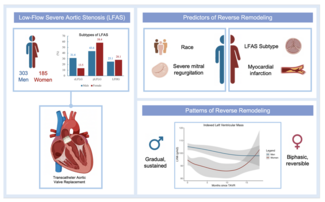

We engaged the RCA again with an 8 Fr JR4 guide and rewired into the acute marginal branch distal to the CTO and into the distal RCA using the same "hairpin wire" technique. We once again encountered significant difficulty delivering equipment to the distal RCA. Several 1.5 mm balloons could not cross. We were finally able to advance a Corsair catheter (Asahi Intecc) (arrow, Figure 2B) to the distal RCA using an anchor balloon technique with a 2.5 mm balloon into a small proximal RCA conus branch (arrowhead, Figure 2B). The Whisper wire (Abbott Vascular) was exchanged for an Ironman wire (Abbott Vascular, arrowhead, Figure 2C), which enabled sequential delivery of 2.0, 2.5, and 3.0 mm balloons and predilation of the entire proximal, mid, and distal RCA. We were then able to deliver three 3.0 mm x 28 mm Xience V everolimus-eluting stents (Abbott Vascular) using a Guideliner catheter (Vascular Solutions, arrow, Figure 2C) for extra guide support. The stents were postdilated with a 3.5 mm non-compliant balloon, providing an excellent final angiographic result (Figure 2D), as confirmed by intravascular ultrasonography. The total fluoroscopy time and air kerma radiation dose were 39.2 minutes and 7.4 Gray, respectively, and 358 mL of contrast were administered. At 1-month follow-up the patient was angina-free and had significantly increased his daily activities.

We engaged the RCA again with an 8 Fr JR4 guide and rewired into the acute marginal branch distal to the CTO and into the distal RCA using the same "hairpin wire" technique. We once again encountered significant difficulty delivering equipment to the distal RCA. Several 1.5 mm balloons could not cross. We were finally able to advance a Corsair catheter (Asahi Intecc) (arrow, Figure 2B) to the distal RCA using an anchor balloon technique with a 2.5 mm balloon into a small proximal RCA conus branch (arrowhead, Figure 2B). The Whisper wire (Abbott Vascular) was exchanged for an Ironman wire (Abbott Vascular, arrowhead, Figure 2C), which enabled sequential delivery of 2.0, 2.5, and 3.0 mm balloons and predilation of the entire proximal, mid, and distal RCA. We were then able to deliver three 3.0 mm x 28 mm Xience V everolimus-eluting stents (Abbott Vascular) using a Guideliner catheter (Vascular Solutions, arrow, Figure 2C) for extra guide support. The stents were postdilated with a 3.5 mm non-compliant balloon, providing an excellent final angiographic result (Figure 2D), as confirmed by intravascular ultrasonography. The total fluoroscopy time and air kerma radiation dose were 39.2 minutes and 7.4 Gray, respectively, and 358 mL of contrast were administered. At 1-month follow-up the patient was angina-free and had significantly increased his daily activities.

Discussion. Our report demonstrates the following: (1) wiring into a side branch at the CTO distal cap and subsequently performing balloon angioplasty into the side branch can restore antegrade flow into the main vessel (“distal open-sesame technique”); (2) the “hairpin wire” technique can be useful in directing a guidewire from the side branch to the main vessel; and (3) use of multiple guide support enhancement techniques and of the Corsair microcatheter (Abbott Vascular) may enable successful lesion crossing, once conventional strategies fail.

The “open sesame” technique was first described by Saito in 4 challenging CTOs.1 The author demonstrated how insertion of stiff wires and balloon inflation of a side branch at the CTO proximal cap facilitated antegrade CTO wiring, likely by inducing a geographic shift of the atherosclerotic plaque. In our case we describe a modification of the open sesame technique, the “distal open sesame technique,” in which a wire is advanced into a side branch at the distal CTO cap. After balloon angioplasty into the side branch, antegrade flow was restored.

After multiple guidewires failed to enter the main vessel distal to the CTO, the "hairpin wire" technique was utilized successfully. A polymer-jacketed wire was bent approximately 3 cm from the wire tip, advanced to the acute marginal branch, and pulled back entering the main vessel. This technique was first described by Kawasaki et al to access an extremely angulated bifurcation, and was given the name “reversed guidewire’’ technique.2 A modification of this technique named “hairpin-trap” technique was recently described for stent retrieval.3 In the current case, the hairpin wire technique was useful in directing a guidewire through a highly angulated acute marginal branch into the mid RCA.